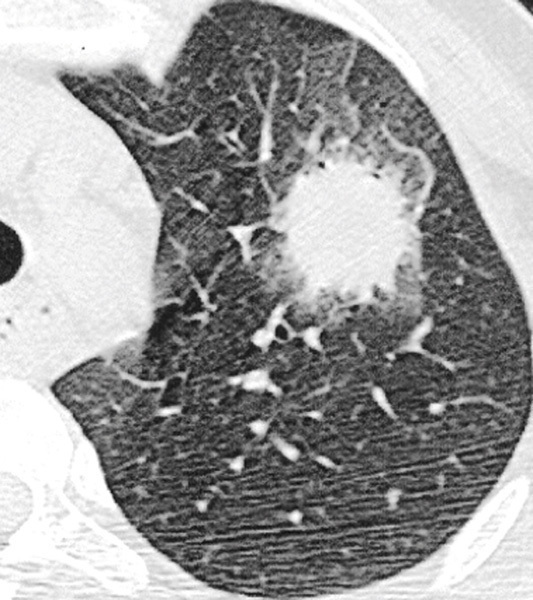

Aspergillose pulmonaire invasive

TDM thoracique. Atteinte pulmonaire de l'aspergillose.